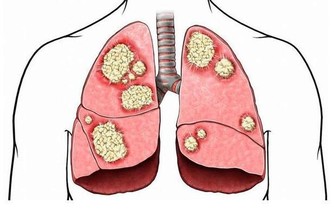

*****2、頭部眩暈*****

起床時頭部眩暈,疼痛,同樣有可能是嚴重疾病發出的信號,經過一整晚的睡眠身體得到良好的調節,大腦也維持健康狀態,起床時精神狀態良好,身體輕鬆,可以正常工作或者學習。

但是,有部分人起床後身體的不適感覺明顯,很可能是大腦部位的血管發生病變,局部的血管因為血液粘稠堵塞或者狹窄,循環無法保持良好,大腦會缺血,缺氧而引發疾病,在影響下就會頭部眩暈或者疼痛。

當然,有部分人大腦動脈粥樣硬化會引發腦供血不足,這種表現也明顯,需要通過正確治療讓大腦循環維持正常。